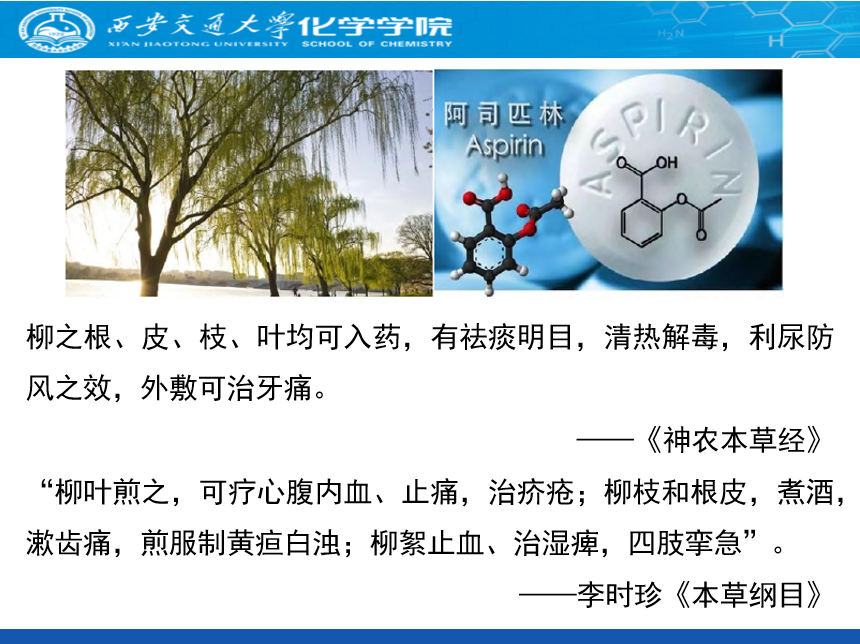

我国古代就有折柳相赠的习俗,用以表达依依惜别之情,其实柳树还有更重要的用途。公元前4世纪,“医学之父”希波克拉底用柳树叶煮汤治头痛,让孕妇咀嚼柳树皮以缓解生产时的疼痛并减轻后续发热症状。1763年,人们发现用柳树皮粉可以治疗疟疾引起的发热。直到1829年,活性成分水杨苷被成功提取,并被发现其在体外有很强的药理活性,为日后研发阿司匹林奠定基础。由于从柳树中提取水杨酸的过程比较复杂,1859年科学工作者第一次人工合成了水杨酸,并再次验证该药物具有良好的解热镇痛作用。但是,随着临床上的广泛应用,人们发现水杨酸可导致胃溃疡、呕吐等不良副作用。1897年,德国拜耳公司的科学家霍夫曼因其父亲身患风湿病,而长期服用水杨酸副作用非常大,故将化合物结构进行改良,合成了乙酰水杨酸。通过动物试验和临床试验,人们发现乙酰水杨酸的解热镇痛作用比水杨酸更好,而且副作用小。1899年,德国拜耳公司将乙酰水杨酸注册专利,并命名为阿司匹林。

勤劳智慧的中华民族在上古时期便有神农尝百草的传说,我国的医药学先贤也在中医四大经典著作之一《神农本草经》、东方药学巨典《本草纲目》中记载了柳树的药用价值,其活性成分即为水杨酸。在实验室条件下,让学生在水杨酸的基础上合成其衍生物——乙酰水杨酸,实现水杨酸化学结构的改进,能够培养学生从化学的视角出发,重新认识中医、中药的作用,增强学生的民族自信心和自豪感。